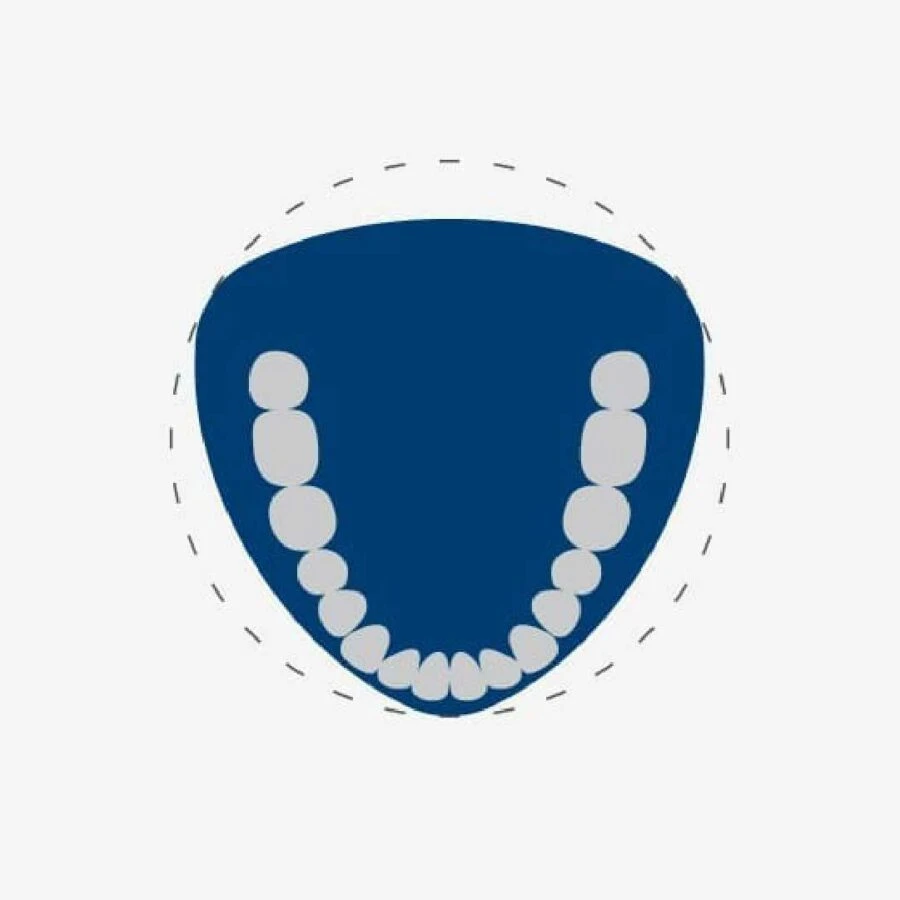

Máy X-quang nha khoa 3D Veraviewepocs R100 đã đột phá đưa ra hình dạng mới của FOV, cho phép đạt được gần nhất hình dạng hàm răng tự nhiên. Việc sử dụng 3D Reuleaux Full Arch FOV cung cấp các hình dáng độc nhất cho việc tạo ảnh toàn bộ hàm.

Trường nhìn máy x-quang nha khoa 3D toàn hàm dạng tam giác

Khu vực tiếp xúc dành cho nhiều Dianostics